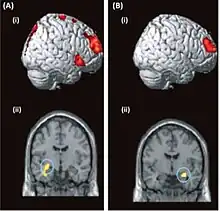

| Brain-imaging data from two patients with dissociative amnesia | |

Brain activity can be assessed functionally for psychogenic amnesia using imaging techniques such as fMRI, PET and EEG, in accordance with clinical data.[6] Some research has suggested that organic and psychogenic amnesia to some extent share the involvement of the same structures of the temporo-frontal region in the brain.[7] It has been suggested that deficits in episodic memory may be attributable to dysfunction in the limbic system,[21] while self-identity deficits have been suggested as attributable to functional changes related to the posterior parietal cortex.[3] To reiterate however, care must be taken when attempting to define causation as only ad hoc reasoning about the aetiology of psychogenic amnesia is possible, which means cause and consequence can be infeasible to untangle.[15]